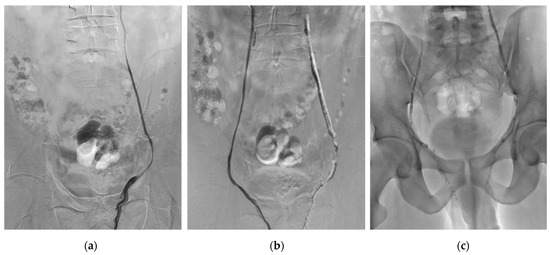

2.4. Embolization Technique